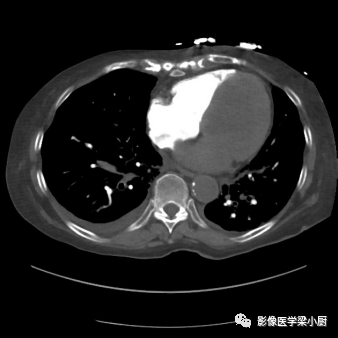

心源性肺水肿,上肺野血管纹理增多,肺内血流重新分布,心影增大,双侧胸腔积液。